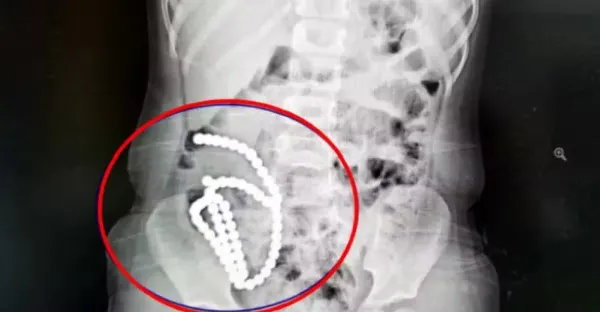

4歲妹妹照X光驚見「肚子整串白珠珠」 媽證實哥哥在玩!醫嘆:一輩子毀了

喬峰傳 • 230次觀看